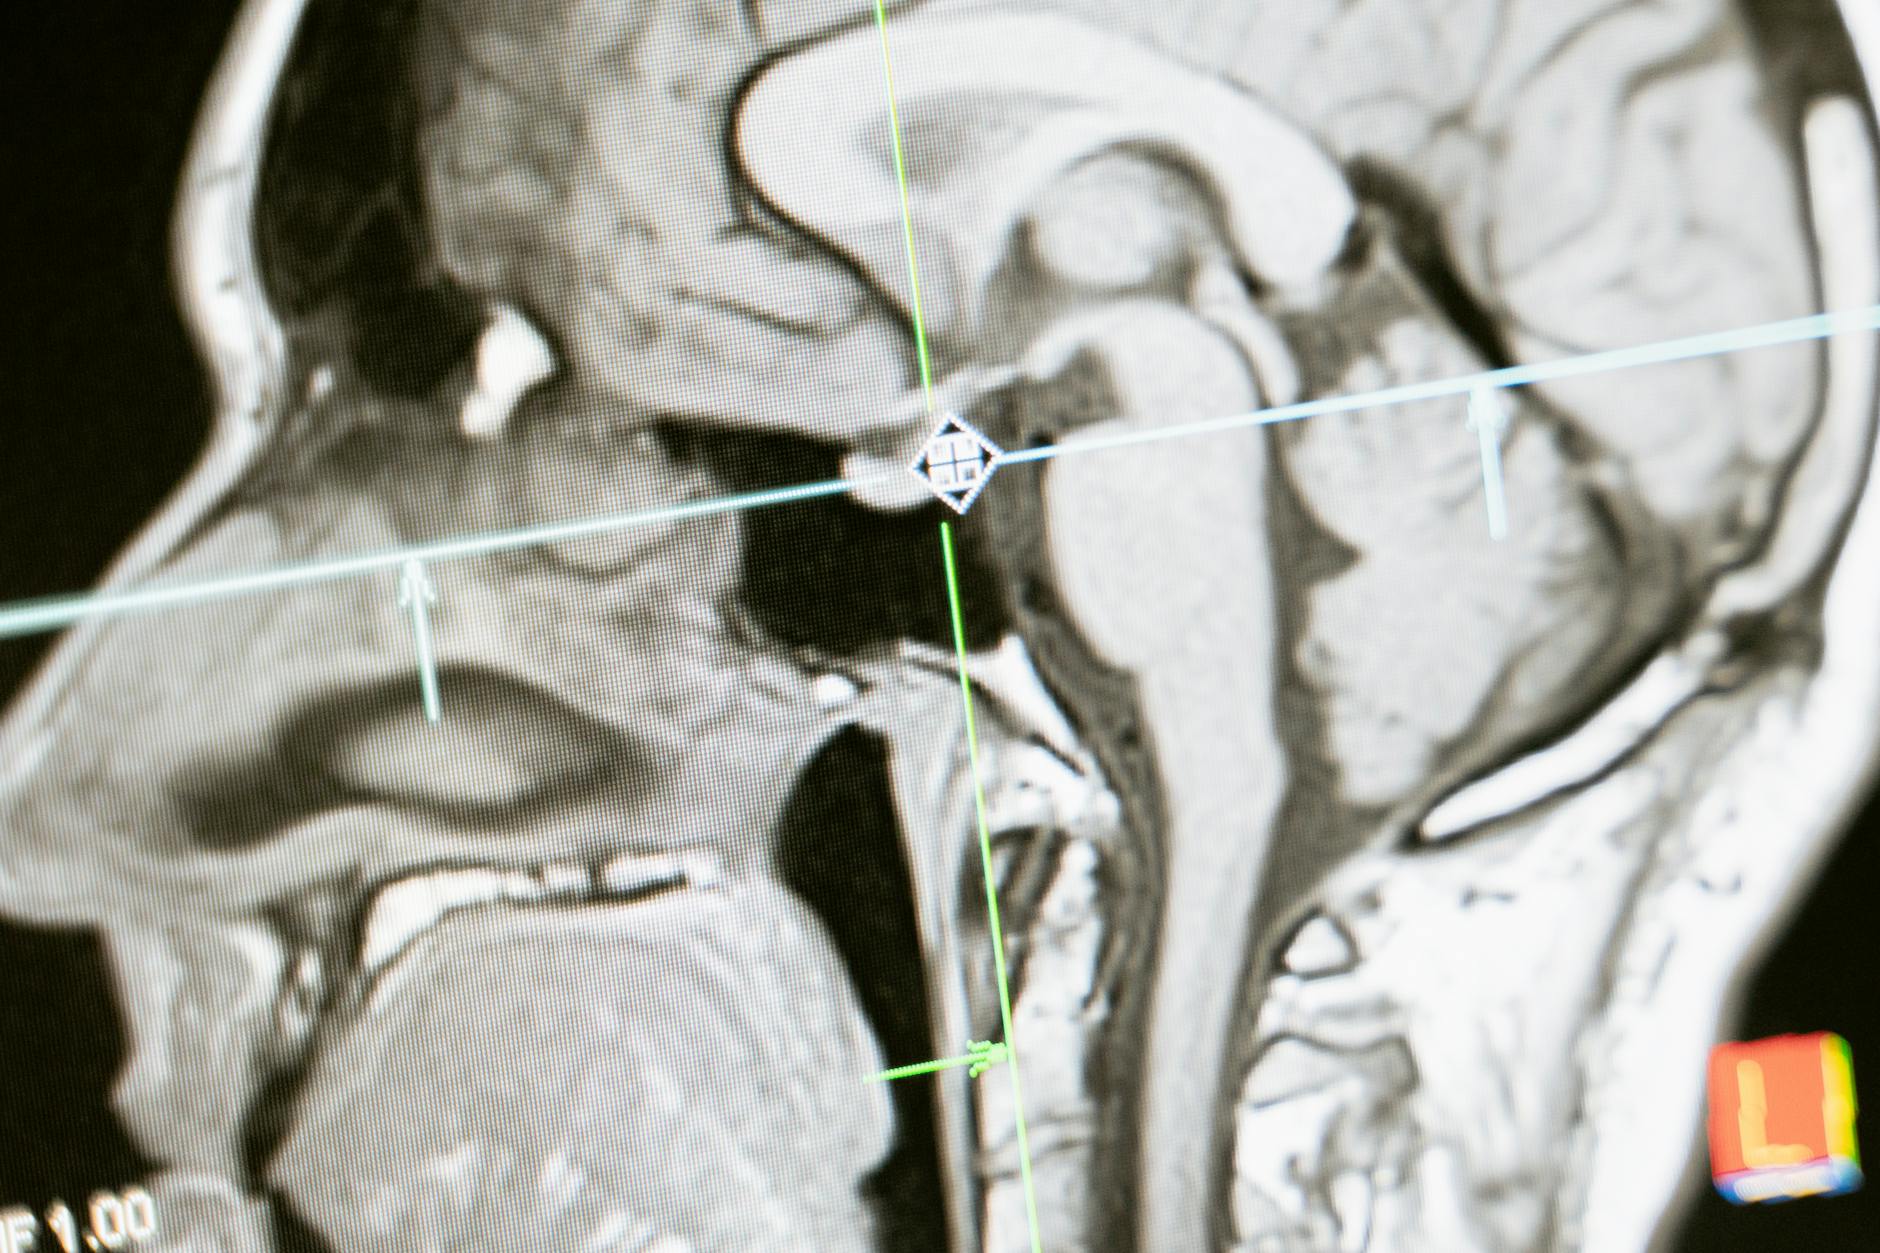

Recent research has begun to reveal why head injuries create such fertile ground for neurodegeneration, and the mechanisms are more complex than simple physical damage to neurons. Three biological pathways have attracted significant scientific attention in the past two years. The first involves tau protein, one of the hallmark features of Alzheimer’s disease. Research from the University of Virginia has shown that even a single mild TBI can accelerate harmful tau accumulation in the brain. Under normal conditions, tau helps stabilize the internal scaffolding of neurons. After injury, tau can become misfolded and begin clumping into tangles that disrupt cell function and eventually kill neurons.

This process may begin immediately after injury but take years or decades to produce noticeable cognitive symptoms. MRI studies from USC have reinforced this connection, showing that gray and white matter degrade in strikingly similar patterns in both TBI patients and Alzheimer’s patients, suggesting shared downstream pathology. The second pathway, published in January 2025 by researchers at the University of Oxford, involves viral reactivation. The study found that repeated head injuries may reactivate dormant herpes simplex virus 1 (HSV-1) in the brain, triggering inflammatory cascades resembling those seen in Alzheimer’s disease. HSV-1 is extremely common, with an estimated two-thirds of the global population carrying it, usually without symptoms. The possibility that mechanical brain trauma could awaken a dormant virus and set off neuroinflammation opens an entirely new avenue of research and, potentially, treatment. If viral reactivation proves to be a significant driver, antiviral medications could theoretically become part of post-TBI care, though this remains speculative.